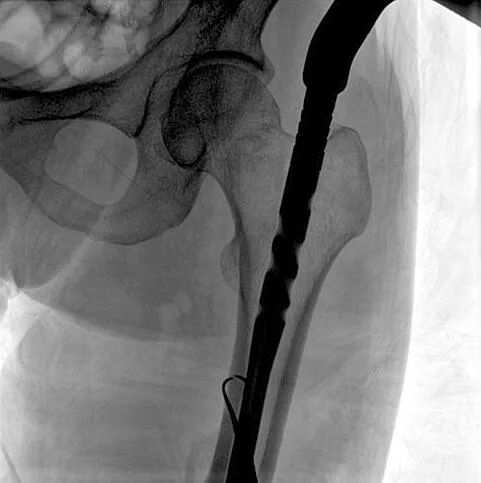

C形臂輔助手術(shù)過程

術(shù)中使用普愛醫(yī)療大平板一體式C形臂進(jìn)行透視,判斷骨折情況及克氏針、髓內(nèi)釘?shù)冉饘僦踩胛锏奈恢茫M(jìn)行調(diào)整。C形臂準(zhǔn)確的術(shù)中定位,大大縮短了手術(shù)的時(shí)間,減輕了患者的痛苦,輔助手術(shù)順利完成。

術(shù)中定位準(zhǔn)確、出血量少,術(shù)后影像顯示股骨移位糾正,恢復(fù)良好力線,手術(shù)效果良好。